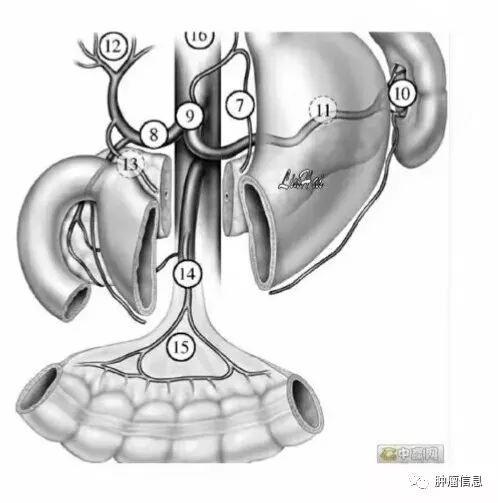

腹部淋巴结按UICC胃癌淋巴结分组分为1-16区:

贲门右淋巴结贲门左淋巴结胃小弯淋巴结胃大弯淋巴结(4sa:胃短血管淋巴结;4sb:胃网膜左血管淋巴结;4d:胃网膜右血管淋巴结)幽门上淋巴结幽门下淋巴结胃左动脉淋巴结肝总动脉淋巴结(8a:肝总动脉前淋巴结;8p:肝总动脉后淋巴结)腹腔干淋巴结脾门淋巴结脾动脉淋巴(11p:脾动脉近端淋巴结;11d:脾动脉远端淋巴结)肝十二指肠韧带淋巴结(12a:肝十二指肠韧带内沿肝动脉淋巴结;12b:肝十二指肠韧带内沿胆管淋巴结;12p:肝十二指肠韧带内沿门静脉后淋巴结)胰头后淋巴结肠系膜淋巴结(14v:肠系膜上静脉淋巴结;14a:肠系膜上动脉淋巴结)结肠中血管淋巴结腹主动脉旁淋巴结(16a1:主动脉裂孔淋巴结;16a2:腹腔干上缘至左肾静脉下缘之间腹主动脉周围淋巴结;16b1:左肾静脉下缘至肠系膜下动脉上缘之间腹主动脉周围淋巴结;16b2:肠系膜下动脉上缘至腹主动脉分叉之间腹主动脉周围淋巴结)

No.14肠系膜根部淋巴结

分为:肠系膜上动脉组(14a)和肠系膜上静脉组(14v)

No.15结肠中动脉旁淋巴结

沿结肠中动脉分布,结肠中动脉较小,CT上很难发现,勾画时可以从受累的横结肠延伸到肠系膜根部血管区域

No.16腹主动脉旁淋巴结

上界:腹腔干上缘下界:L3下缘(肠系膜下动脉上缘)